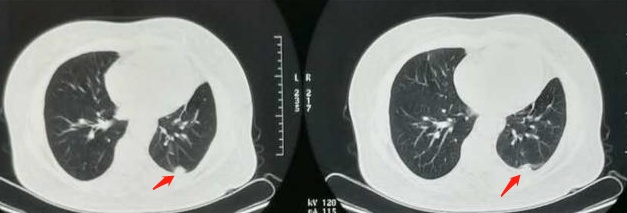

上图这位老太太,肺腺癌广泛转移,下过三次病危通知书,服用靶向药物治疗,第3年复查的时候,病灶显著缩小:

老太太说感谢有这么好的药,也感谢医生!当年一个病房里的7位病友只剩下她一个人了,她要坚持下去,活着就有希望!